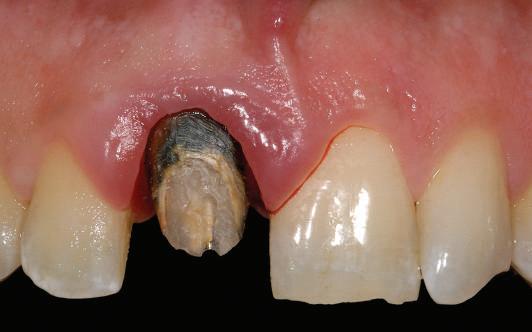

CAZ CLINIC

Pacientul EG, 45 ani, fumător, s-a prezentat în clinică pentru rezolvarea multiplelor probleme estetice și funcționale. Planul de tratament general a vizat afectarea parodontală generalizată, îndepărtarea tuturor restaurărilor protetice vechi, extracția dinților compromiși, retratamentele endodontice și reconstituirile de bonturi necesare pentru dinții stâlpi, precum și realizarea unor restaurări protetice înșurubate implantar la nivelul celor 4 cadrane dar și restaurări unidentare la nivelul bonturilor dentare restante.

Conform informațiilor oferite de CBCT, pe pozițiile molarilor 36 și 37 au fost inserate două implanturi Ankylos (Dentsply Implants) C/X A 11 (diametru 3.5 mm, lungime 11 mm).

Datorită stabilității primare la inserare de aproximativ 35 Ncm pentru ambele implanturi, am optat pentru înșurubarea bonturilor intermediare conice Balance Base Narrow Straight GH 3.0 și vindecare transgingivală (fig. 2, 3). Inserarea acestor stâlpi s-a realizat la un cuplu de forțe de 25Ncm, cu ajutorul unei chei dinamometrice, aplicându-se ulterior cape de protecție (fig. 4). Vindecarea transgingivală postoperatorie a decurs fără complicații.